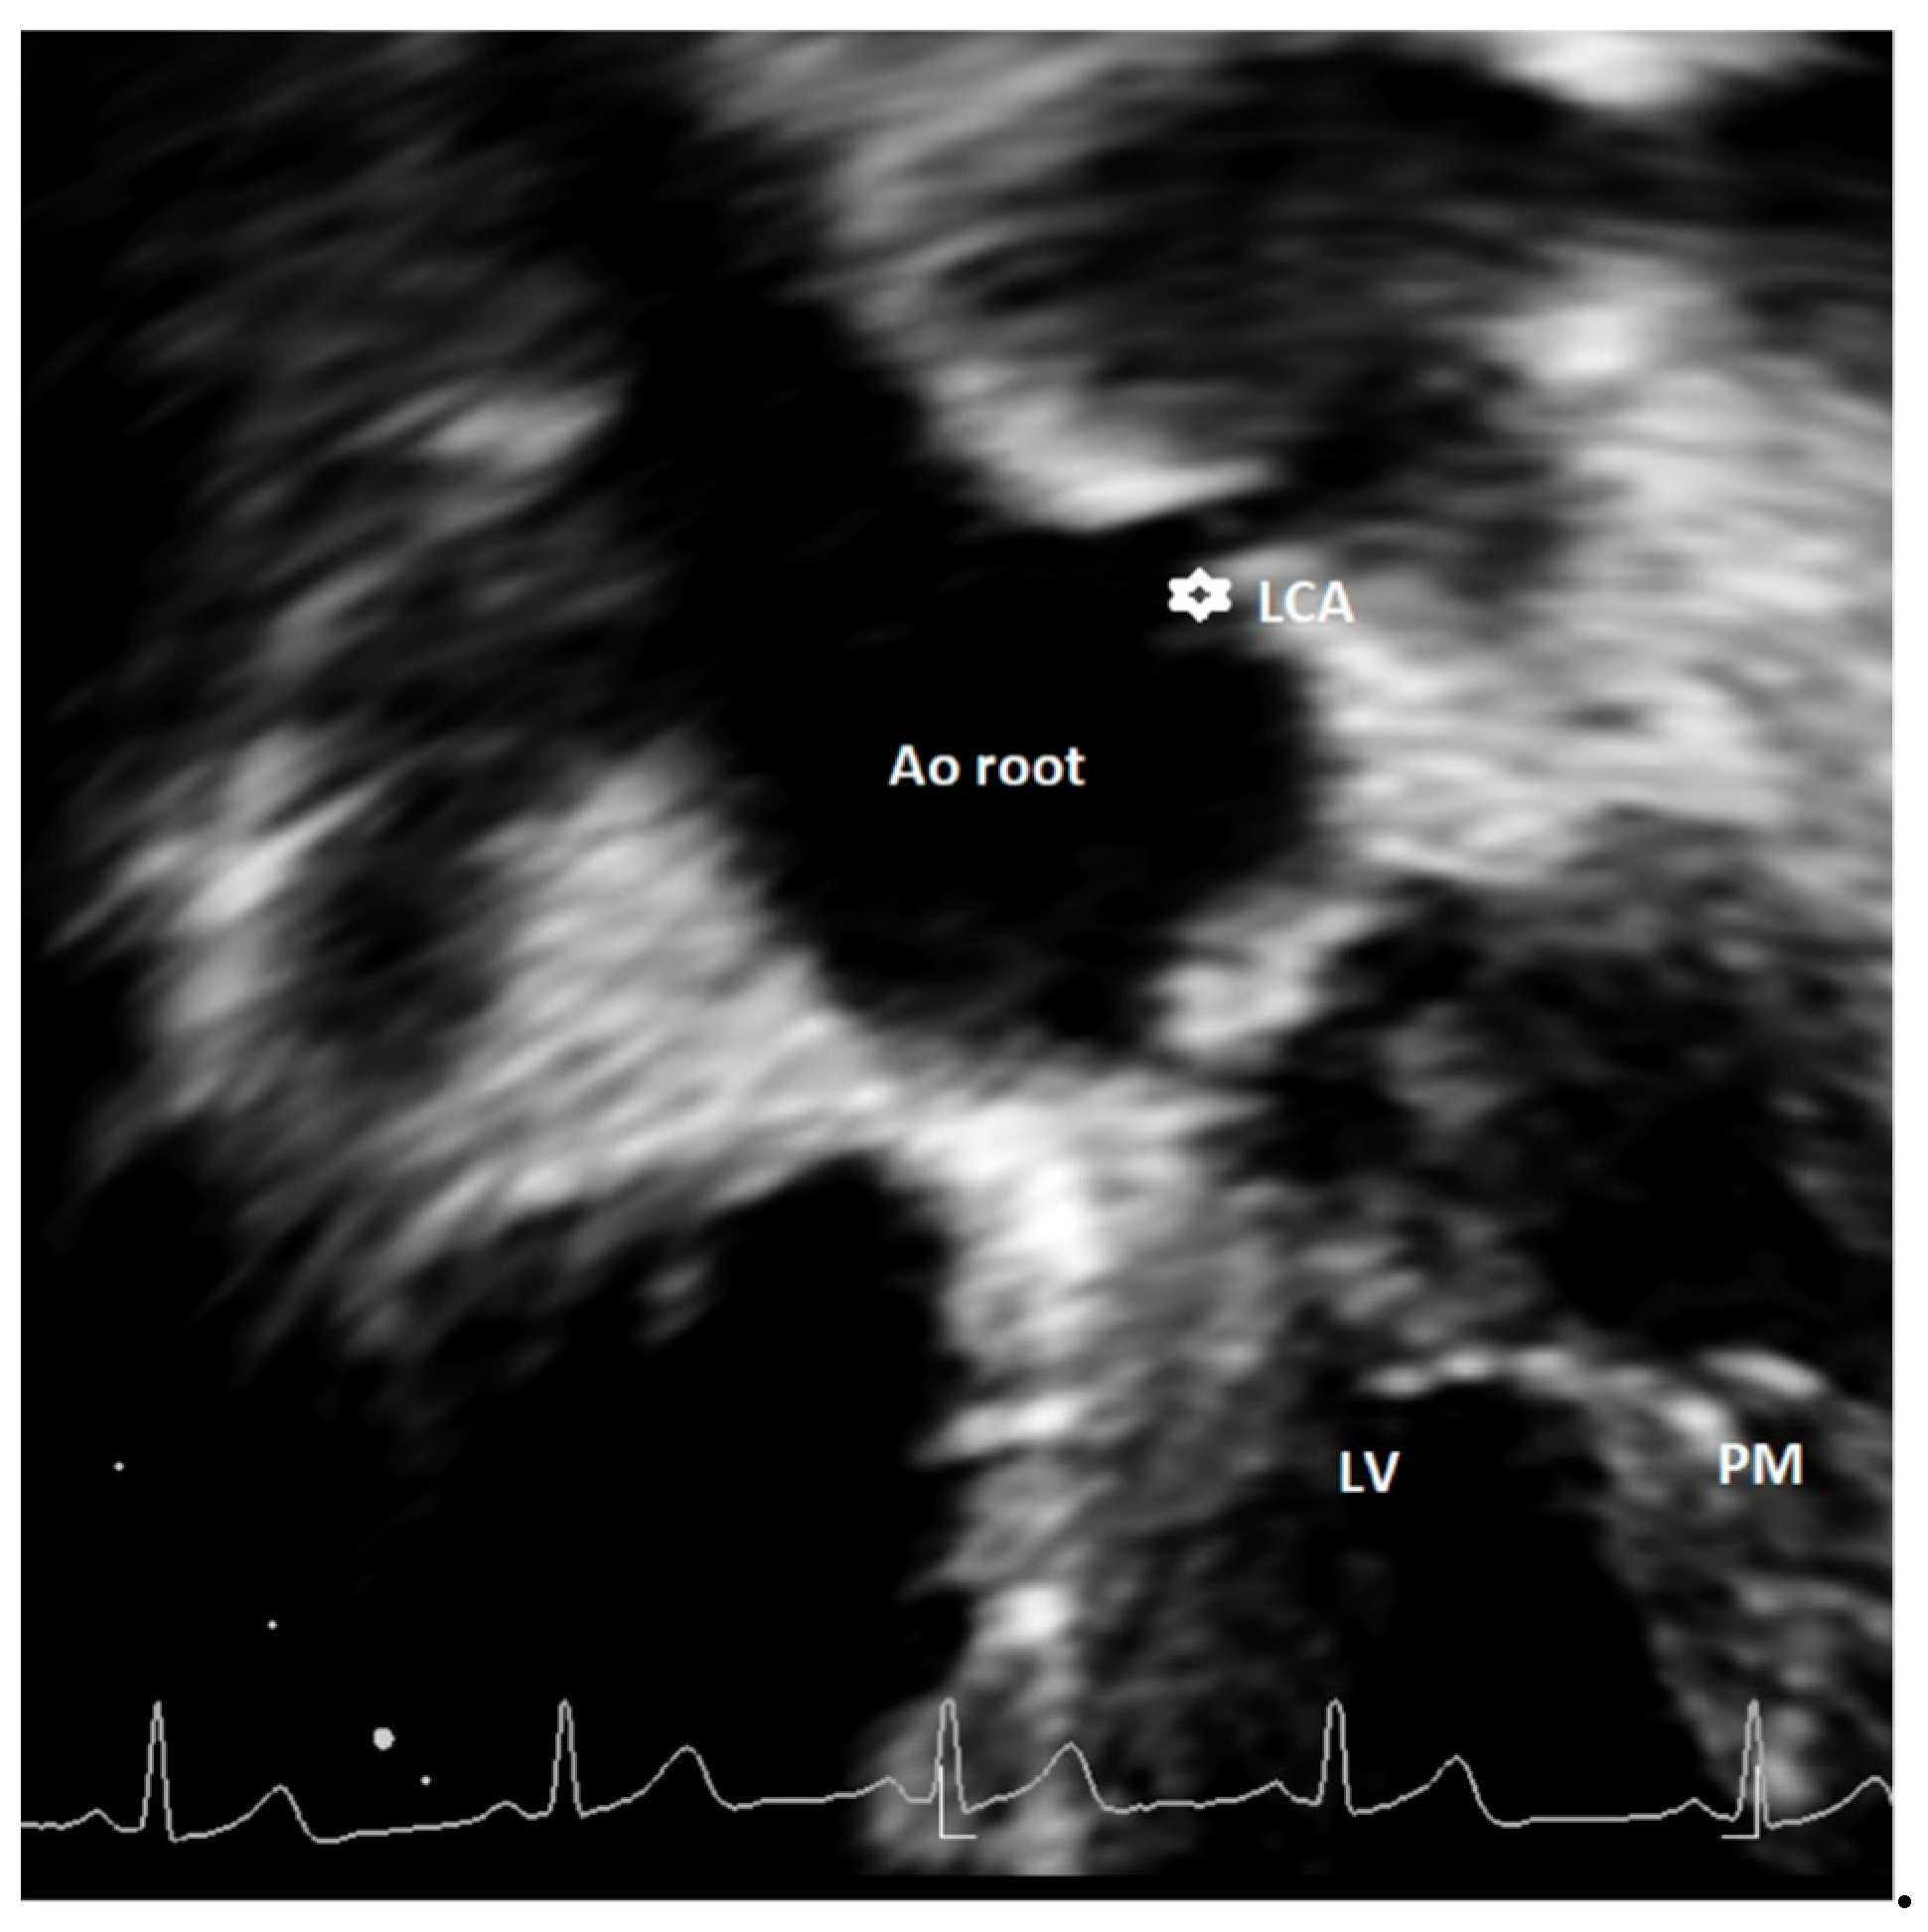

Figure 4. Modified apical 5-chamber view showing high take-off of left coronary artery (asterisk). This is a case of an asymptomatic 14-year-old female, with incidental diagnosis of bicuspid aortic valve. Ao = aorta, LCA = left common coronary artery, LV = left ventricle; PM = papillary muscle.

Discrepancies exist in the definition of major and minor AAOCAs, especially regarding the classification of a high take-off of coronary artery origin. Unfortunately, limited echocardiographic data are currently available in the literature [13,14,23]. Furthermore, most of the CT studies adopted a different definition as compared to echocardiographic articles. Indeed, in most cases, CT studies defined high take-off as a height >1 cm or >20% the depth of the sinus above STJ [26], a height >0.25 cm above the sinutubular junction, and a minority any height above the STJ [26]. Echocardiographic studies all used the latter definition, identifying the high take-off as an origin above or distal to the STJ [13,14,23]. The use of different cut-offs to define a high take-off has the consequence of affecting prevalence [33]; indeed, in CT studies where the definition of a height >1 cm or >20% the depth of the sinus above sinutubular junction was used, the incidence of RCA high take-off was 0.202%. Conversely, in those that employed a height >0.25 cm above the sinutubular junction as a definition, it decreased to 0.199% [33]. When the high take-off of RCA was defined as any height of origin above STJ, the prevalence of this defect increased [33] up to 0.364% [26]. In echocardiographic studies that used the latter definition, the reported incidence of RCA high take-off was even higher than in CT studies, ranging from 0.36% [23] to 1.14% [13]. This definition may overestimate the prevalence of high take-off but, most importantly, it may have the consequence to classify benign variants as malignant anomalies potentially at risk of SCD [33]. As recently reviewed [26], 3 of 12,899 (0.023%) cases of high take-off coronaries that originated more than one centimeter above the sinutubular junction were associated with SCD. Notably, although preferable in adults, the use of fixed criteria (such as 1 cm above the sinutubular junction) may have relevant limitations in children where aortic dimensions are smaller than in adults; therefore, some authors [44] proposed the adoption of relative criteria, such as coronary orifices that arise 120% or more of the depth of the sinus of Valsalva or 20% or more the depth of the sinus above the STJ. A comprehensive evaluation of a high take-off of coronary arteries should also include other important characteristics, such as the presence of slit-like ostium, stenosis, the interarterial course, and intramural course [26,33,34,35]. Notably, a high take-off associated with acute angulation from the aorta, an intramural or an interarterial course comprising 4% of the defects, are more at risk for the development of SCD [26]. This specific characteristic may be studied by echocardiography [13], but this imaging technique has inherent limitations for an accurate definition of these characteristics that need a comprehensive multimodality approach for their definition, as suggested by the current recommendations [26]. Furthermore, based on previously published studies, no clear indications exist for the appropriate acoustic window to be used for other coronary anomalies, such as the high take-off of coronary arteries, and particularly for LCA. Current recommendations [26] suggest using a coronal subcostal view to visualize LCA origin; however this window can be easily utilized only in neonates and children. We propose in this article an additional acoustic window that may allow for evaluation of high take-off of LCA by using a modified apical five-chamber view (see Figure 4). So far, we have tested this projection in a limited number of cases with suspicion of LCA high take-off or when origin of LCA was not seen by conventional short-axis and parasternal long-axis views, with encouraging results.